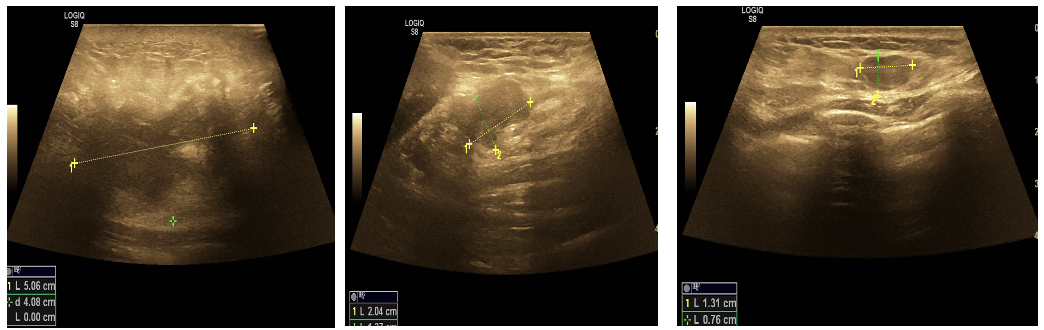

• 乳腺+腋窝淋巴结超声(2023年10月6日 ):双乳腺增生症;右乳多发实性结节(BI-RADS-4a);左乳多发实性结节(BI-RADS-3);右侧腋中、下组多个淋巴结肿大(建议活检);左侧腋窝多个淋巴结可见,个别淋巴结肿大。

图 2023年10月6日乳腺+腋窝淋巴结超声